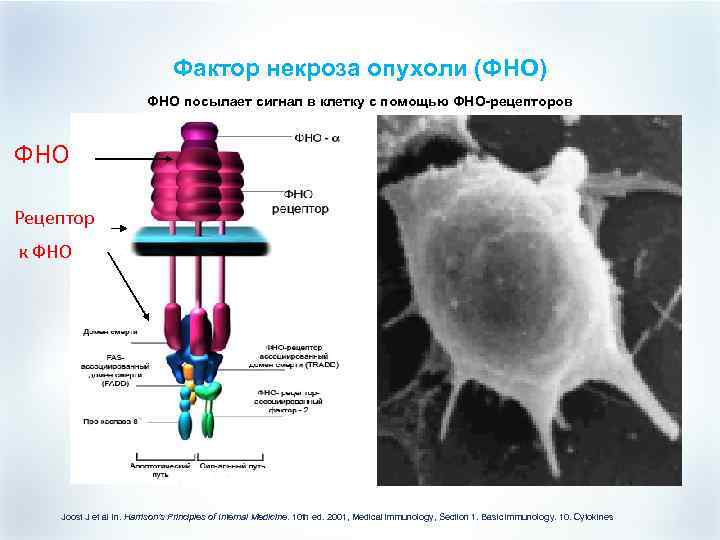

Фактор некроза опухоли (ФНО) ФНО посылает сигнал в клетку с помощью ФНО-рецепторов ФНО Рецептор к ФНО Joost J et al in. Harrison’s Principles of Internal Medicine. 10 th ed. 2001, Medical immunology, Section 1. Basic immunology. 10. Cytokines

Фактор некроза опухоли (ФНО) ФНО посылает сигнал в клетку с помощью ФНО-рецепторов ФНО Рецептор к ФНО Joost J et al in. Harrison’s Principles of Internal Medicine. 10 th ed. 2001, Medical immunology, Section 1. Basic immunology. 10. Cytokines